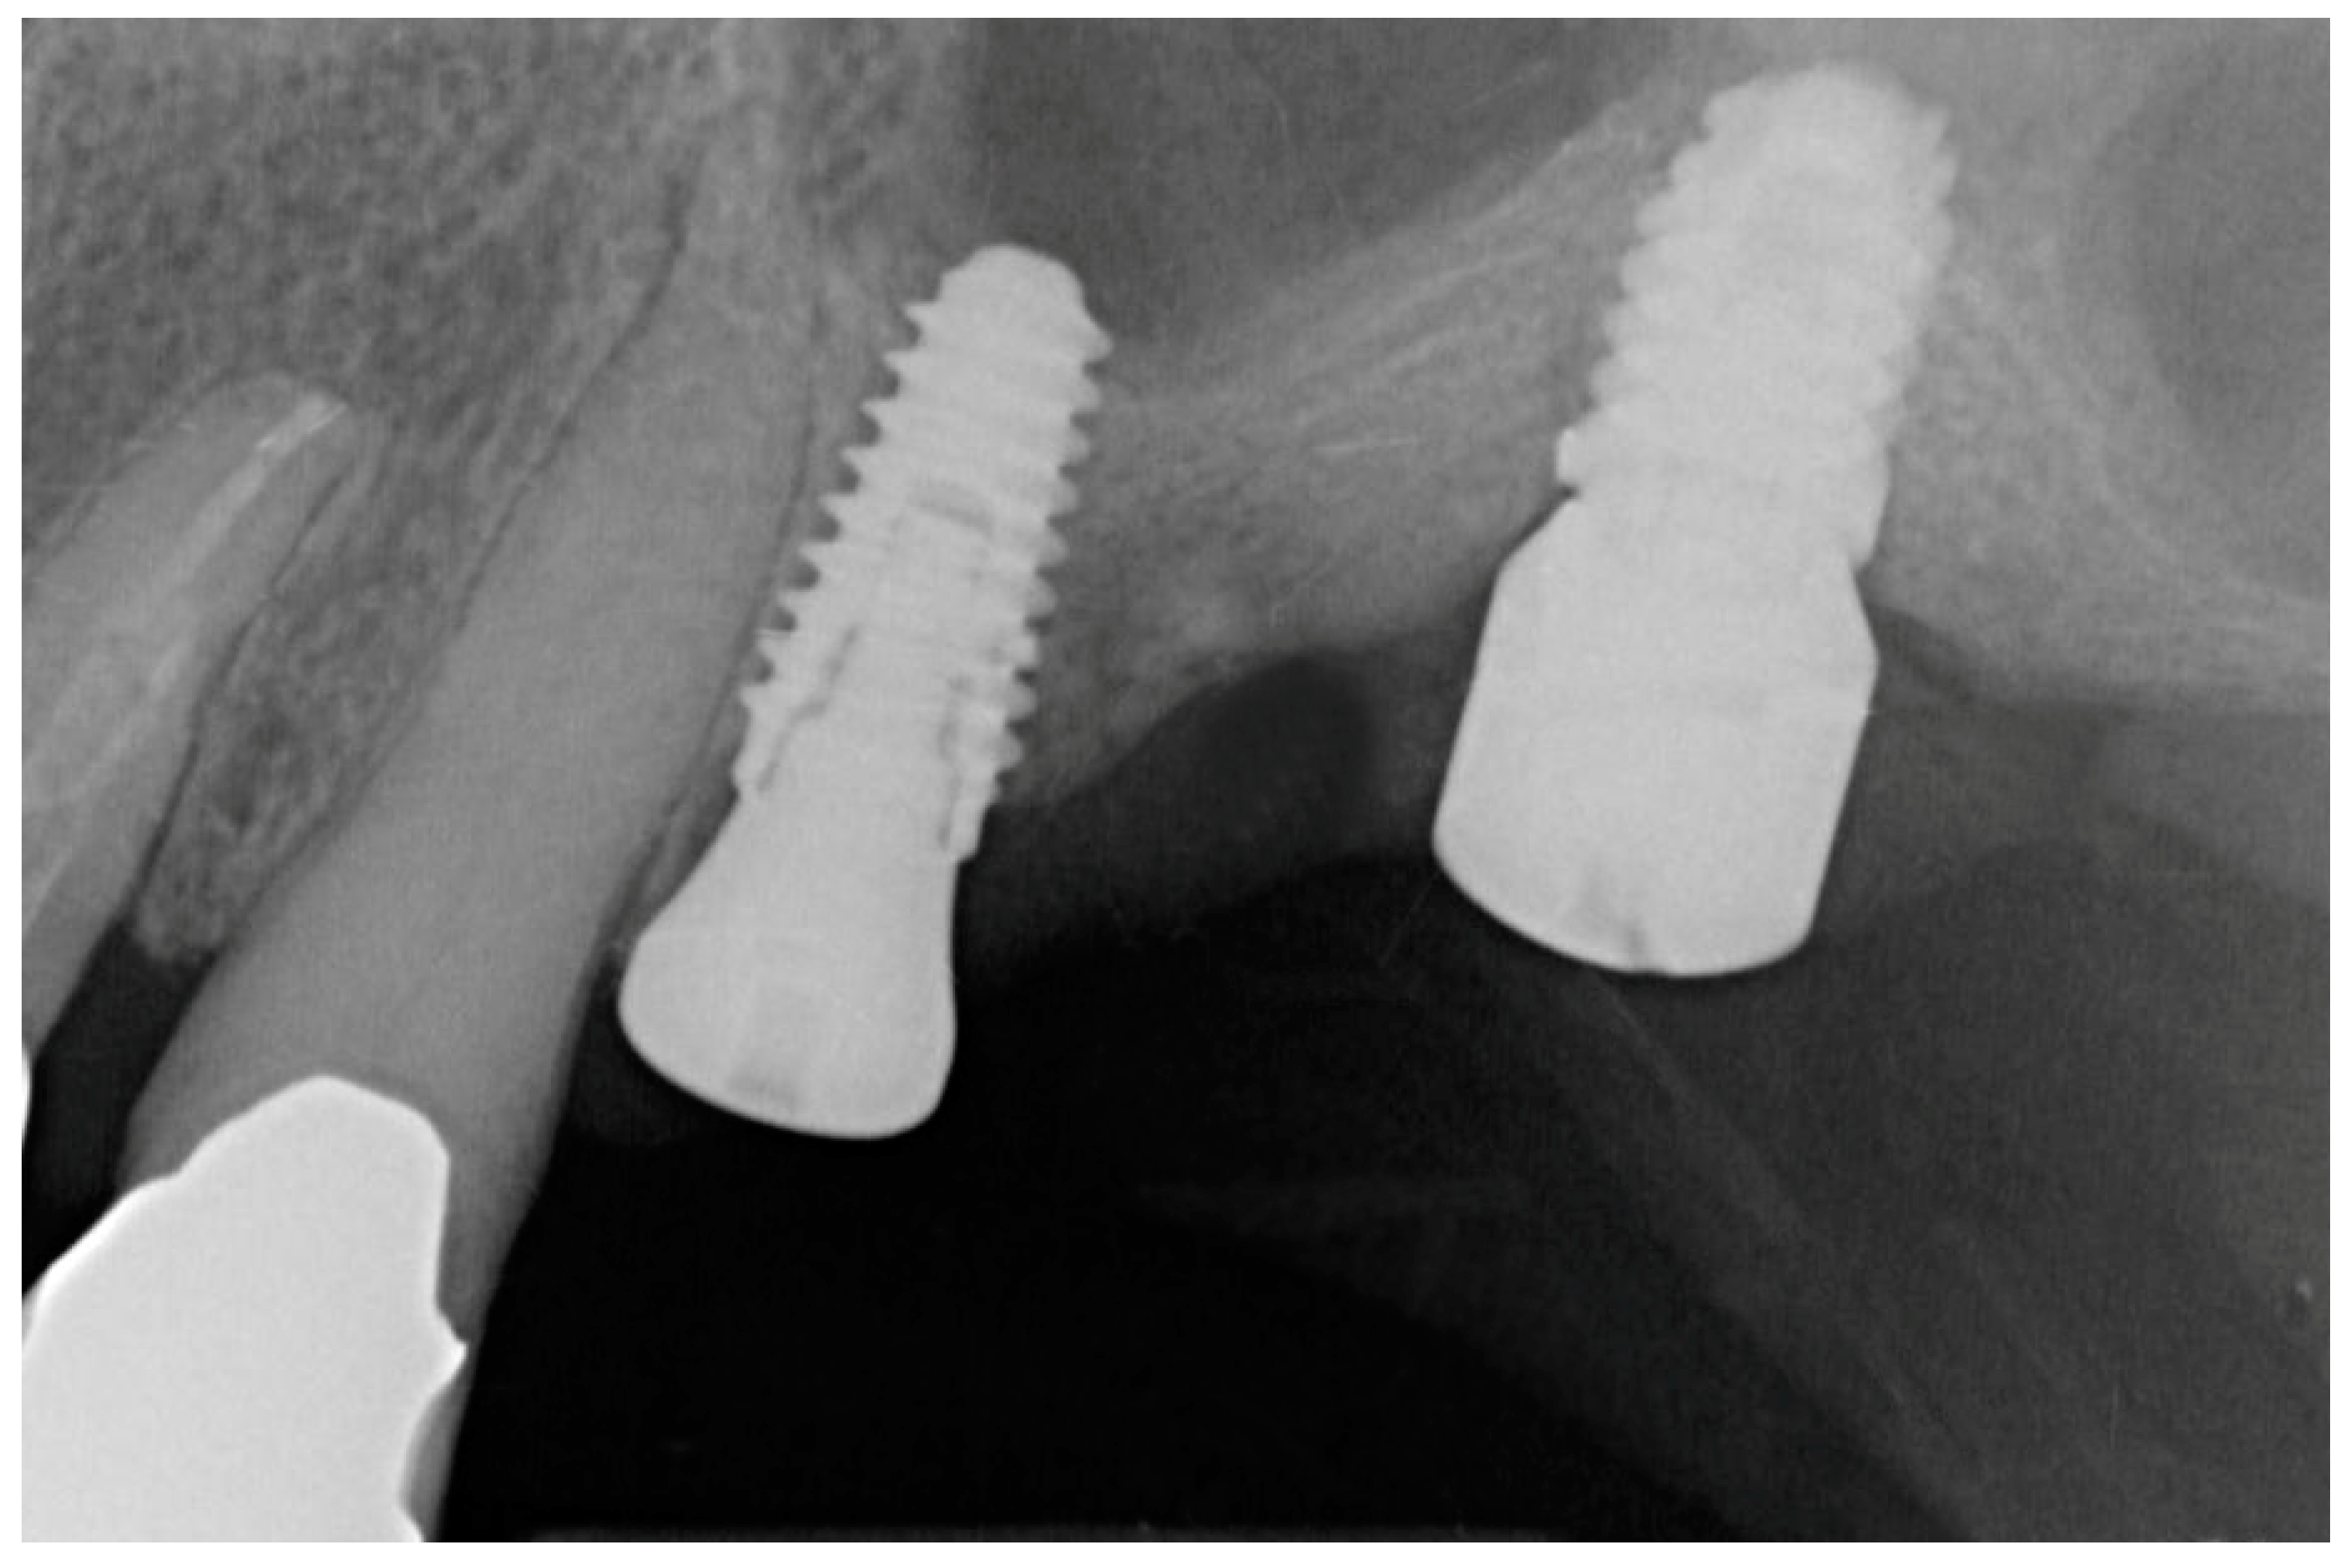

3. Results